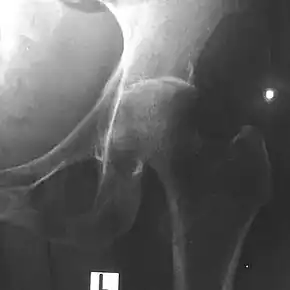

Depending on the course of infection, other severe manifestations develop. About 1 to 5% of those infected develop inflammation of the brain and brain covering or collection of pus in the brain; 14 to 28% develop bacterial inflammation of the kidneys, kidney abscess or prostatic abscesses; 0 to 30% develop neck or salivary gland abscesses; 10 to 33% develop liver, spleen, or paraintestinal abscesses; 4 to 14% develop septic arthritis and osteomyelitis.[1] Rare manifestations include lymph node disease resembling tuberculosis,[9] mediastinal masses, collection of fluid in the heart covering,[3] abnormal dilatation of blood vessels due to infection,[1] and inflammation of the pancreas.[3] In Australia, up to 20% of infected males develop prostatic abscess characterized by pain during urination, difficulty in passing urine, and urinary retention requiring catheterisation.[1] Rectal examination shows inflammation of the prostate.[3] In Thailand, 30% of the infected children develop parotid abscesses.[1] Encephalomyelitis can occur in healthy people without risk factors. Those with melioidosis encephomyelitis tend to have normal computed tomography scans, but increased T2 signal by magnetic resonance imaging, extending to the brain stem and spinal cord. Clinical signs include: unilateral upper motor neuron limb weakness, cerebellar signs, and cranial nerve palsies (VI, VII nerve palsies and bulbar palsy). Some cases presented with flaccid paralysis alone.[3] In northern Australia, all melioidosis with encephalomyelitis cases had elevated white cells in the cerebrospinal fluid (CSF), mostly mononuclear cells with elevated CSF protein.[9]

Various imaging modalities can also help with the diagnosis of melioidosis. In acute melioidosis with the spreading of the bacteria through the bloodstream, the chest X-ray shows multifocal nodular lesions. It may also show merging nodules or cavitations. For those with acute melioidosis without the spread to the bloodstream, chest X-ray shows upper-lobe consolidation or cavitations. In chronic melioidosis, the slow progression of upper-lobe consolidation of the lungs resembles tuberculosis. For abscesses located in other parts of the body apart from the lungs, especially in the liver and spleen, CT scan has higher sensitivity when compared with an ultrasound scan. In liver and splenic abscesses, an ultrasound scan shows "target-like" lesions, while CT scan shows "honeycomb sign" in liver abscesses. For melioidosis involving the brain, MRI has higher sensitivity than a CT scan in diagnosing the lesion. MRI shows ring-enhancing lesions for brain melioidosis.[9]